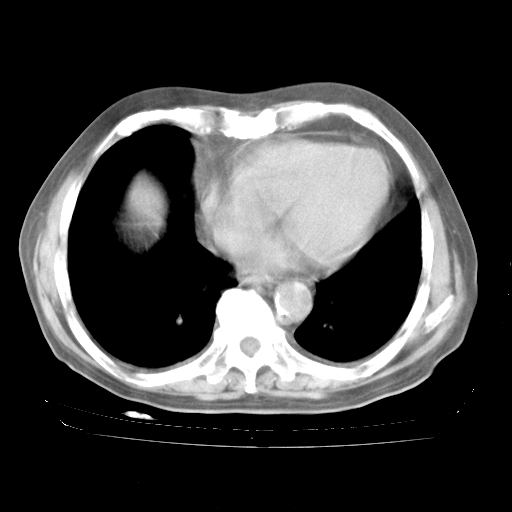

4月28日肺部CT——再次出现类似去年5月9日——透光度降低,“间质性”改变。

4月28日肺部CT